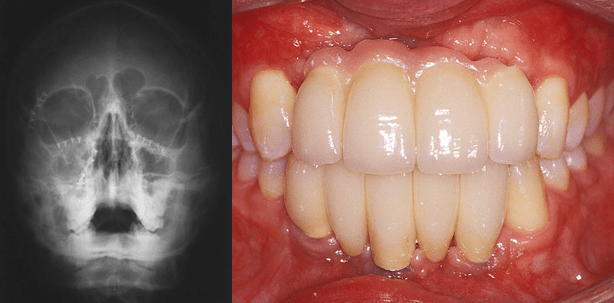

Nach neuerlicher Implantatabformung im Ober- und Unterkiefer (Abb. 16a und b, Abb. 17) zur Übertragung der aktuellen Weichteilsituation (Abb. 18) auf die Meistermodelle wurden mit CAD/CAM-Technik Implantataufbauten gefertigt: Im Oberkiefer wurden bei hohem ästhetischen Anspruch individuelle, mit einer Titanbasis verklebte Zirkonoxidaufbauten, im Unterkiefer individuelle Aufbauten aus Titan (Fa. Straumann) gewählt (Abb. 19). Entsprechend der Empfehlung eines Zirkonoxid-Konsenses17 wurde eine zementierbare prothetische Arbeit geplant: CAD/CAM-gefertigte Brückengerüste aus Zirkonoxid (Fa. Wieladent) wurde mit e.max-Keramik (Fa. Ivoclar Vivadent) verblendet, wobei im Oberkiefer in Analogie zum Provisorium auch rosa Keramik für einen möglichst natürlichen Aspekt verwendet wurde. Bei sehr engen Implantatzwischenräumen wurden Führungsrillen für Superfloss (Fa. Oral-B) bzw. sehr dünne Interdentalbürstchen eingearbeitet (Abb. 20). Die Abbildungen 21 und 22 zeigen die konventionell zementierte Arbeit im Mund. Der Patient kommt damit gut zurecht und ist zufrieden. Die Röntgen-Einzelbilder dokumentieren den einwandfreien Sitz der verblockten Kronen bzw. der Brücke, aber auch einen weiteren vertikalen Knochenverlust: Die Bone Level-Implantate ragen etwas über das Knochenniveau (Abb 23a bis c). Regelmäßige klinische und radiologische Kontrollen sind vorgesehen.